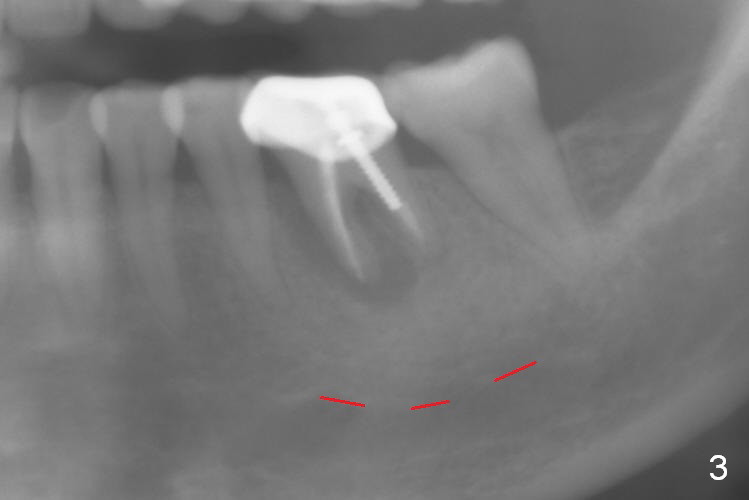

A 58-year-old lady has a long-standing periapical lesion with several episodes of acute infection (Fig.1-3, taken 10, 9 and 2 years ago, respectively). Explore the socket for size and wall integrity (Clindamycin). If the bony defect is not extensive, place a longest implant (18 mm bone-level, 20 mm tissue-level) with moderate diameter (5.5, 6 mm). Otherwise use a shorter, but wider tapered implant (7x12 mm (bone-level), 7 or 8x17 mm (tissue-level)). If the socket is extremely large, consider using 7 or 8 x20 mm cylindrical tissue-level implant. Use Bicon 2 mm pilot drill with extension to measure the socket depth and obtain 3-6 mm new bone or until 20 mm (gingival margin). Take PA. The 1st option is to use UF 3-4.7x18 mm drills at 50 RPM. Make sure that the depth is reached (septum crestal level) and check osteotomy wall integrity after each drill. Then place a 5 or 5.5x16 or 18 mm implant (Fig.6). The 2nd and 3rd options are shown in Fig.4 and 5. Due to severe infection and pain, a shorter implant is placed.